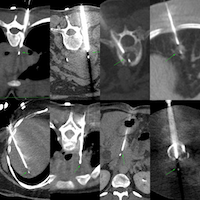

I will be discussing these 6 biopsy cases from Jan 2026, across different levels of difficulty.

Here is a video of the 6 cases that I am going to discuss.

7 cases of different levels of difficulty discussed live on 08 Jan 2026